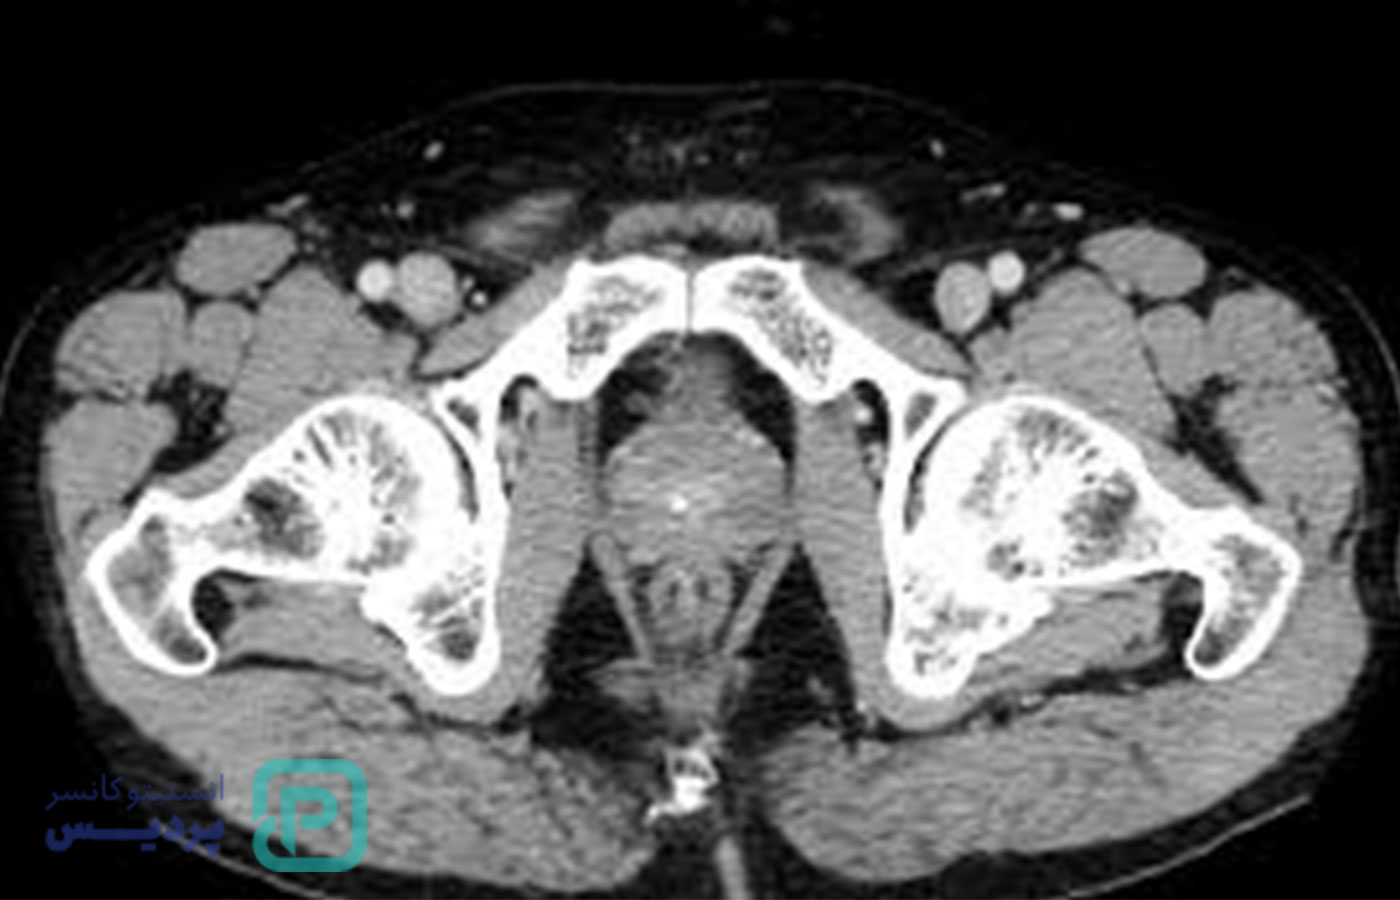

سونوگرافی پروستات (یا همان TRUS) یک آزمایش تصویربرداری است که از امواج صوتی استفاده میکند. در این روش، یک پروب کوچک و روانشده داخل مقعد قرار میگیرد تا پزشک بتواند اندازه، شکل و ساختار پروستات را بهصورت تصویری مشاهده کند و بررسیهای دقیقتری انجام دهد.

این روش کاملاً بدون اشعه است (برخلاف سیتیاسکن یا رادیولوژی)، در اکثر موارد بدون درد یا فقط با فشار خفیف موقتی همراه است و معمولاً طی 10 تا 20 دقیقه انجام میشود.

روش اول: سونوگرافی شکمی (Transabdominal)

طبق استاندارد دانشگاه علوم پزشکی ورشو، این روش بدون نیاز تهاجمی داشتن به سادگی انجام میگیردش:

پروب (فرکانس 2–5 مگاهرتز) به آرامی روی شکم جلو استخوان عانه قرار داده میشود و با حرکت فنری، تصویر پروستات از طریق مثانه دریافت میشود

ابعاد پروستات (طول × عرض × ارتفاع) اندازهگیری و حجم آن با فرمول حجم بیضوی محاسبه میشود

روش دوم: سونوگرافی ترانسرکتال (TRUS)

یکی از دقیقترین روشهای بررسی پروستات و راهنمای بیوپسی:

پروب محافظدار (شبیه انگشت) با ژل روانشونده وارد مقعد شده و با اسکن از زوایای مختلف تصاویر پروستات گرفته میشود